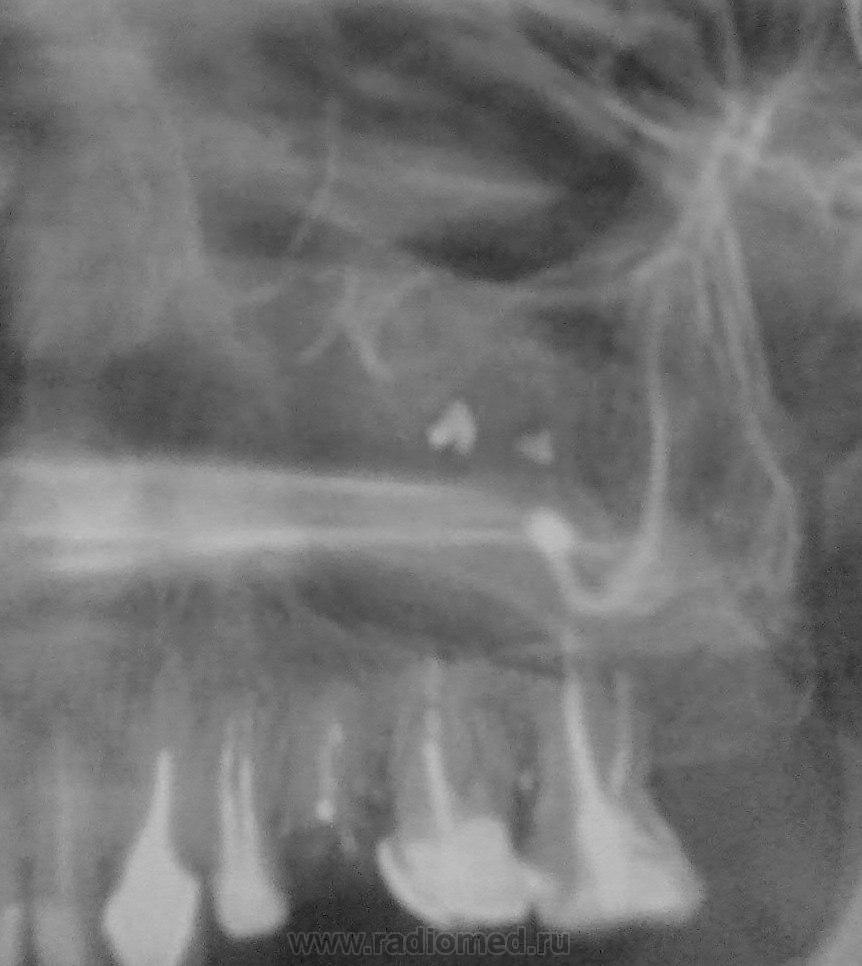

Пол пациента: Женский пол Тип патологии: Другое Область исследования: Челюстно-лицевая область и шея Молодая женщина. Диагноз при направлении - "хронический левосторонний гайморит" В принципе все ясно, но поскольку, как говорится, "есть варианты", то хотелось бы услышать мнение коллег https://radiomed.ru/sites/default/files/styles/case_slider_image/public/user/2667/v2v.jpg?itok=x51CXrcG https://radiomed.ru/sites/default/files/styles/case_slider_image/public/user/2667/v3v.jpg?itok=iK9ItfJZ ID:29230 Чт, 06/06/2013 - 16:05 #1 А.Ю. Не на сайте Был на сайте: 11 лет 10 месяцев назад Зарегистрирован: 03.10.2012 - 08:43 Публикации: 10 В области зуб 2.7 выведен пломбировочный материал в области ВЧП, вокруг пл.материала вероятнее всего образуются мицетомы. Одонтогенный левосторонний гайморит. Мицетома левой ВЧП. Конультация ЧЛХ. Чт, 06/06/2013 - 18:33 #2 stovbav Не на сайте Был на сайте: 2 года 2 месяцев назад Зарегистрирован: 20.12.2009 - 17:28 Публикации: 7066 Ну вот....уже "вариантов" и нет))))....Вы практически дословно повторили мое заключение)))) Болезни ног: виды, симптомы, причины, профилактика и лечение Чт, 06/06/2013 - 20:33 #3 Катенёв Валенти... Не на сайте Был на сайте: 7 лет 1 неделя назад Зарегистрирован: 22.03.2008 - 22:15 Публикации: 54876 Красивое подтверждение. Чт, 06/06/2013 - 20:34 #4 Катенёв Валенти... Не на сайте Был на сайте: 7 лет 1 неделя назад Зарегистрирован: 22.03.2008 - 22:15 Публикации: 54876 Мицетому тоже выставили в заключении Виктор Григорьевич? Чт, 06/06/2013 - 20:46 #5 stovbav Не на сайте Был на сайте: 2 года 2 месяцев назад Зарегистрирован: 20.12.2009 - 17:28 Публикации: 7066 Катенёв Валентин Львович wrote: Мицетому тоже выставили в заключении Виктор Григорьевич? Написал буквально так в конце протокола:" Прошу учесть возможность развития на этом фоне мицетомы". Болезни ног: виды, симптомы, причины, профилактика и лечение Пт, 07/06/2013 - 17:08 #6 И.Бондаренко Не на сайте Был на сайте: 3 дня 4 часа назад Зарегистрирован: 13.09.2011 - 22:55 Публикации: 9206 Понимаю, что мицетома грибы, но как её можно выставить? Во рту много разной бяки. Пт, 07/06/2013 - 17:40 #7 stovbav Не на сайте Был на сайте: 2 года 2 месяцев назад Зарегистрирован: 20.12.2009 - 17:28 Публикации: 7066 И.Бондаренко wrote: Понимаю, что мицетома грибы, но как её можно выставить? Во рту много разной бяки. Рентгенологически - да практически никак...но, учитывая то, что на ТАКОМ фоне это бывает, то на эту возможность внимание и акцентировано. Болезни ног: виды, симптомы, причины, профилактика и лечение

В области зуб 2.7 выведен пломбировочный материал в области ВЧП, вокруг пл.материала вероятнее всего образуются мицетомы. Одонтогенный левосторонний гайморит. Мицетома левой ВЧП. Конультация ЧЛХ.

Написал буквально так в конце протокола:" Прошу учесть возможность развития на этом фоне мицетомы".

Рентгенологически - да практически никак...но, учитывая то, что на ТАКОМ фоне это бывает, то на эту возможность внимание и акцентировано.